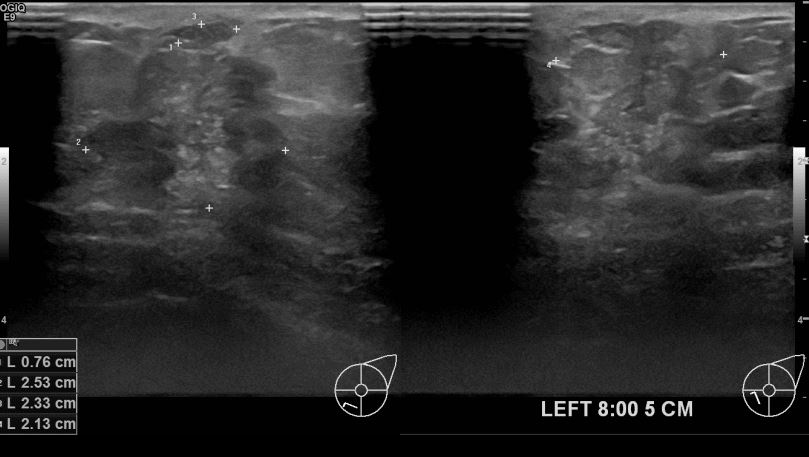

아산유외과개원후 710번째 유방암진단

상기환자 건진상 이상소견으로 조직검사권유받고 내원하신 70대 여성분으로 좌측유방멍울 조직검사시행후 유방암 진단되었습니다